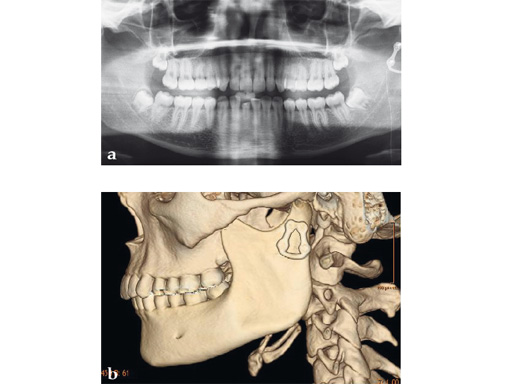

Case 1

Case provided by Celso Palmieri, Shreveport, LA, USA

Case 2

Case provided by Michael Rasse, Innsbruck, Austria